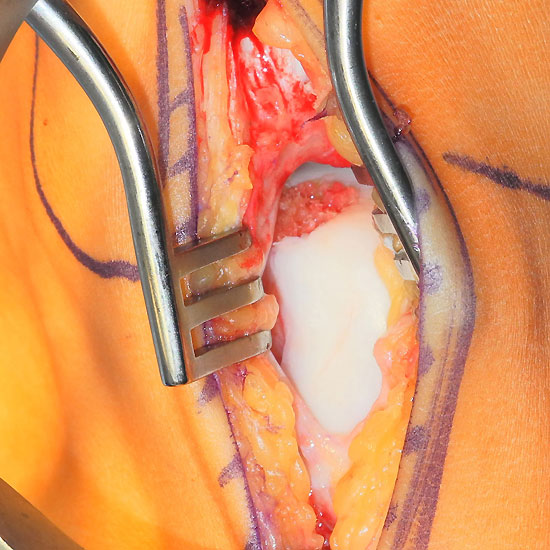

Operationstechnik (Fotos und Video)

Je nach Lage des Knorpeldefektes sind verschiedene Zugänge möglich. Ziel ist einen guten Zugang zum Defekt zu erreichen bei gleichzeitiger Vermeidung einer Innenknöchelosteotomie.

Die Darstellung der weiteren Operationstechnik erfolgt am Beispiel eines medialen Zugangs bei einer Osteochondrosis dissceans mit subchondraler Zyte der medialen Talusschulter (siehe MRT Abbildung 1).

Ist der umliegende Knorpel sehr dick oder liegt nur eine Defektzone mit 1-2 mm Tiefe vor, so kann die Kollagenmatrix auch gedoppelt in Sandwich-Technik implantiert werden. Beide Matrices werden mit der rauhen Oberfläche knochenseitig und der glatten Oberfläche gelenkseitig eingeklebt.